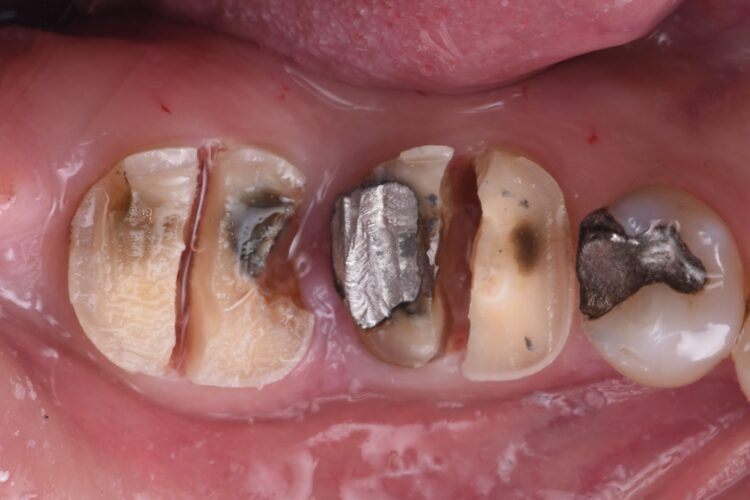

A 57-year-old male patient presented by referral with two failing molars – the LR6 and LR7. The patient had a clear medical history, and both molars exhibited extensive caries and heavy restorations.

The failing teeth were sectioned and extracted atraumatically to preserve the surrounding bone. The sockets were thoroughly debrided using Lucas curettes to remove any residual infection or granulation tissue.